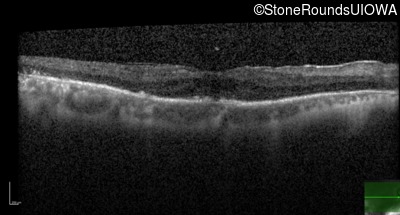

Age at visit: 66 years

OD OS

Age at visit: 68 years